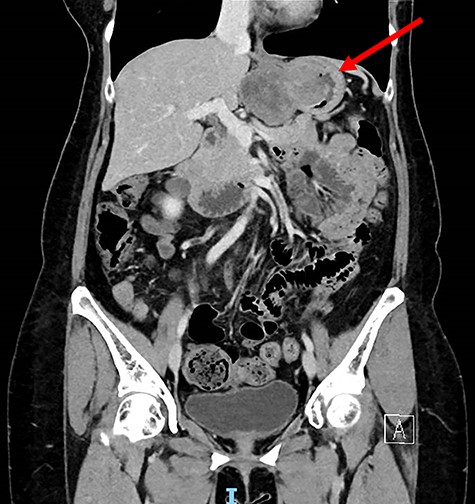

A 56-year-old lady presented with per rectal bleeding and 4 kg weight lost over 1 month. Oesophagogastroduodenoscopy (OGD) performed revealed a large gastric submucosal tumour over the lesser curve (Fig. 1). The proximal margin of the tumour is <1 cm from the GEJ, whereas the distal margin is in the mid lesser curve, about 5 cm proximal to the incisura. Endoscopic ultrasound with fine-needle aspiration performed confirmed the submucosal tumour to be GIST.

Computed tomography thorax abdomen pelvis performed showed a 4.2 × 8.0 × 5.3 cm transmural mass with prominent luminal and exophytic components at the gastric cardia and GEJ (Fig. 2). There were otherwise no enlarged lymph nodes or distant metastases.